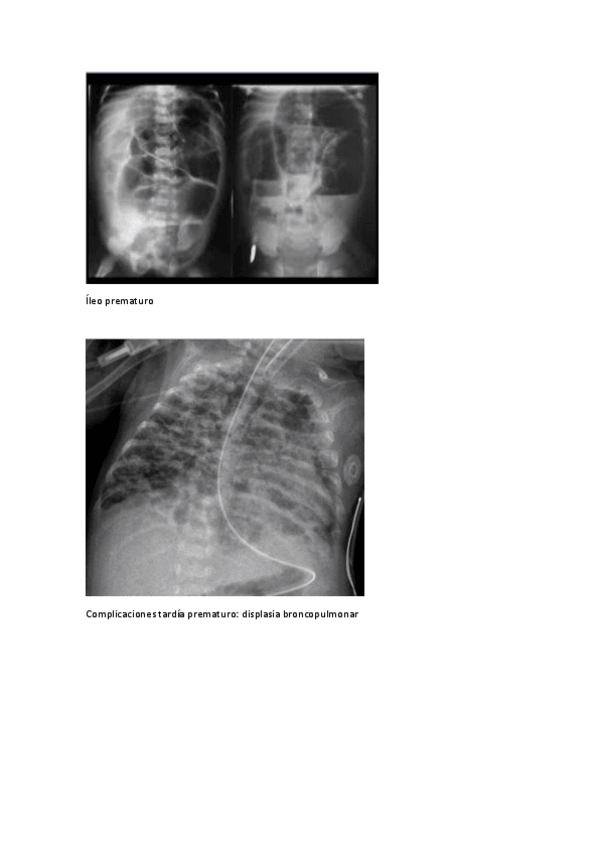

He publicado nuevos practicas de 5º PEDIATRÍA Y CIRUGÍA PEDIÁTRICA I: 2024-Seminario-Semiologia-radiologica-en-neonatologia.pdf

12 páginas